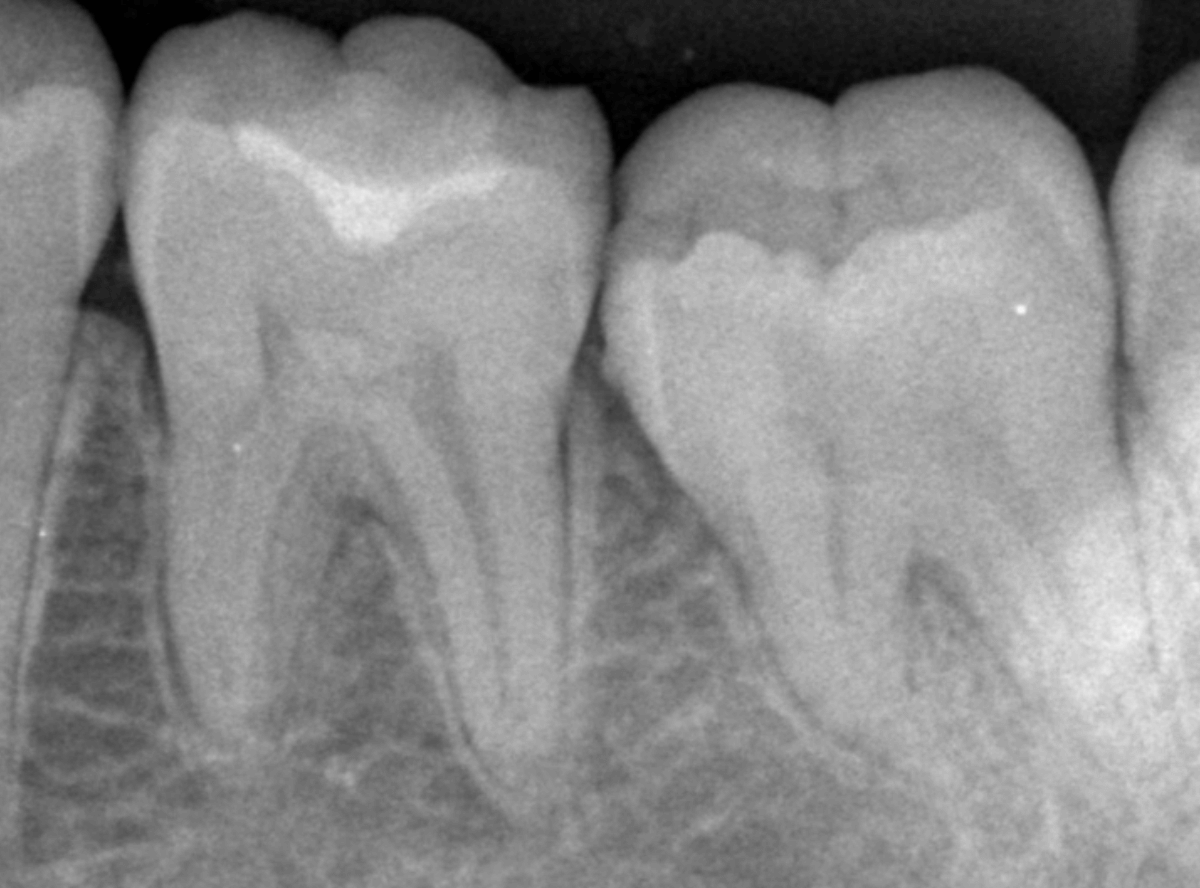

Case.17 レントゲンにはっきり写らないレジンの中の虫歯を削って調べる2

今回も、下の奥歯の虫歯を治療した例です。

特に症状はありませんが、以前に治療したレジンが劣化してすり減っているのと、少し中が黒く透けて見えて、虫歯になっているのが怪しいです。

青いラインが歯の神経です。

以前の虫歯が深めだったようで、レジンが深めにつめてあるのがわかります。

その下がうっすらと虫歯っぽい影になっています(赤いライン)。

虫歯になっているか微妙なラインですが、レジンも劣化していますので、患者さんにご説明して治療することになりました。

レントゲンで虫歯と思われる部分をレジンを除去しました。

見た目には虫歯かどうかはっきりわかりません。

う蝕検知液で染め出します。

うっすらと赤く染色されました。

レントゲン写真と同じく、レジンの下で静かに虫歯が進行し始めていたようです。

もともと深めの虫歯だった部分なので、早いうちに治療が進められてよかったです。